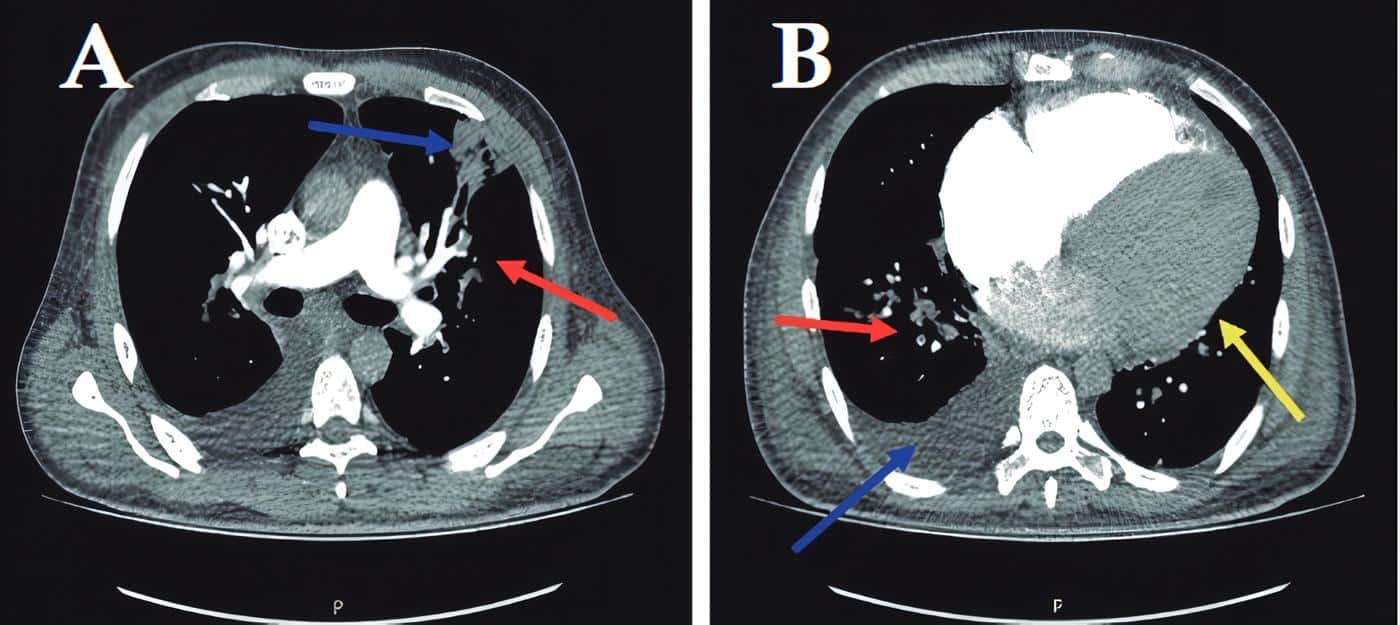

Computed Angio-Tomography of the chest corroborated thrombus and wedge infarction (Figure 2).

Figure 2. Computed angiotomography of the chest with contrast, axial view. A The red arrow shows the location of the central opacifi cation defect, which corresponds to thrombi in the segmental branch for the superior lingular segment, the blue arrow indicates a pleural-based wedge infarction in this same segment. B The red arrow shows the location of the central opacifi cation defect, which corresponds to thrombi in the posterolateral segmental branch of the right lower lobe. The blue arrow shows right pleural eff usion, and the yellow arrow shows cardiomegaly